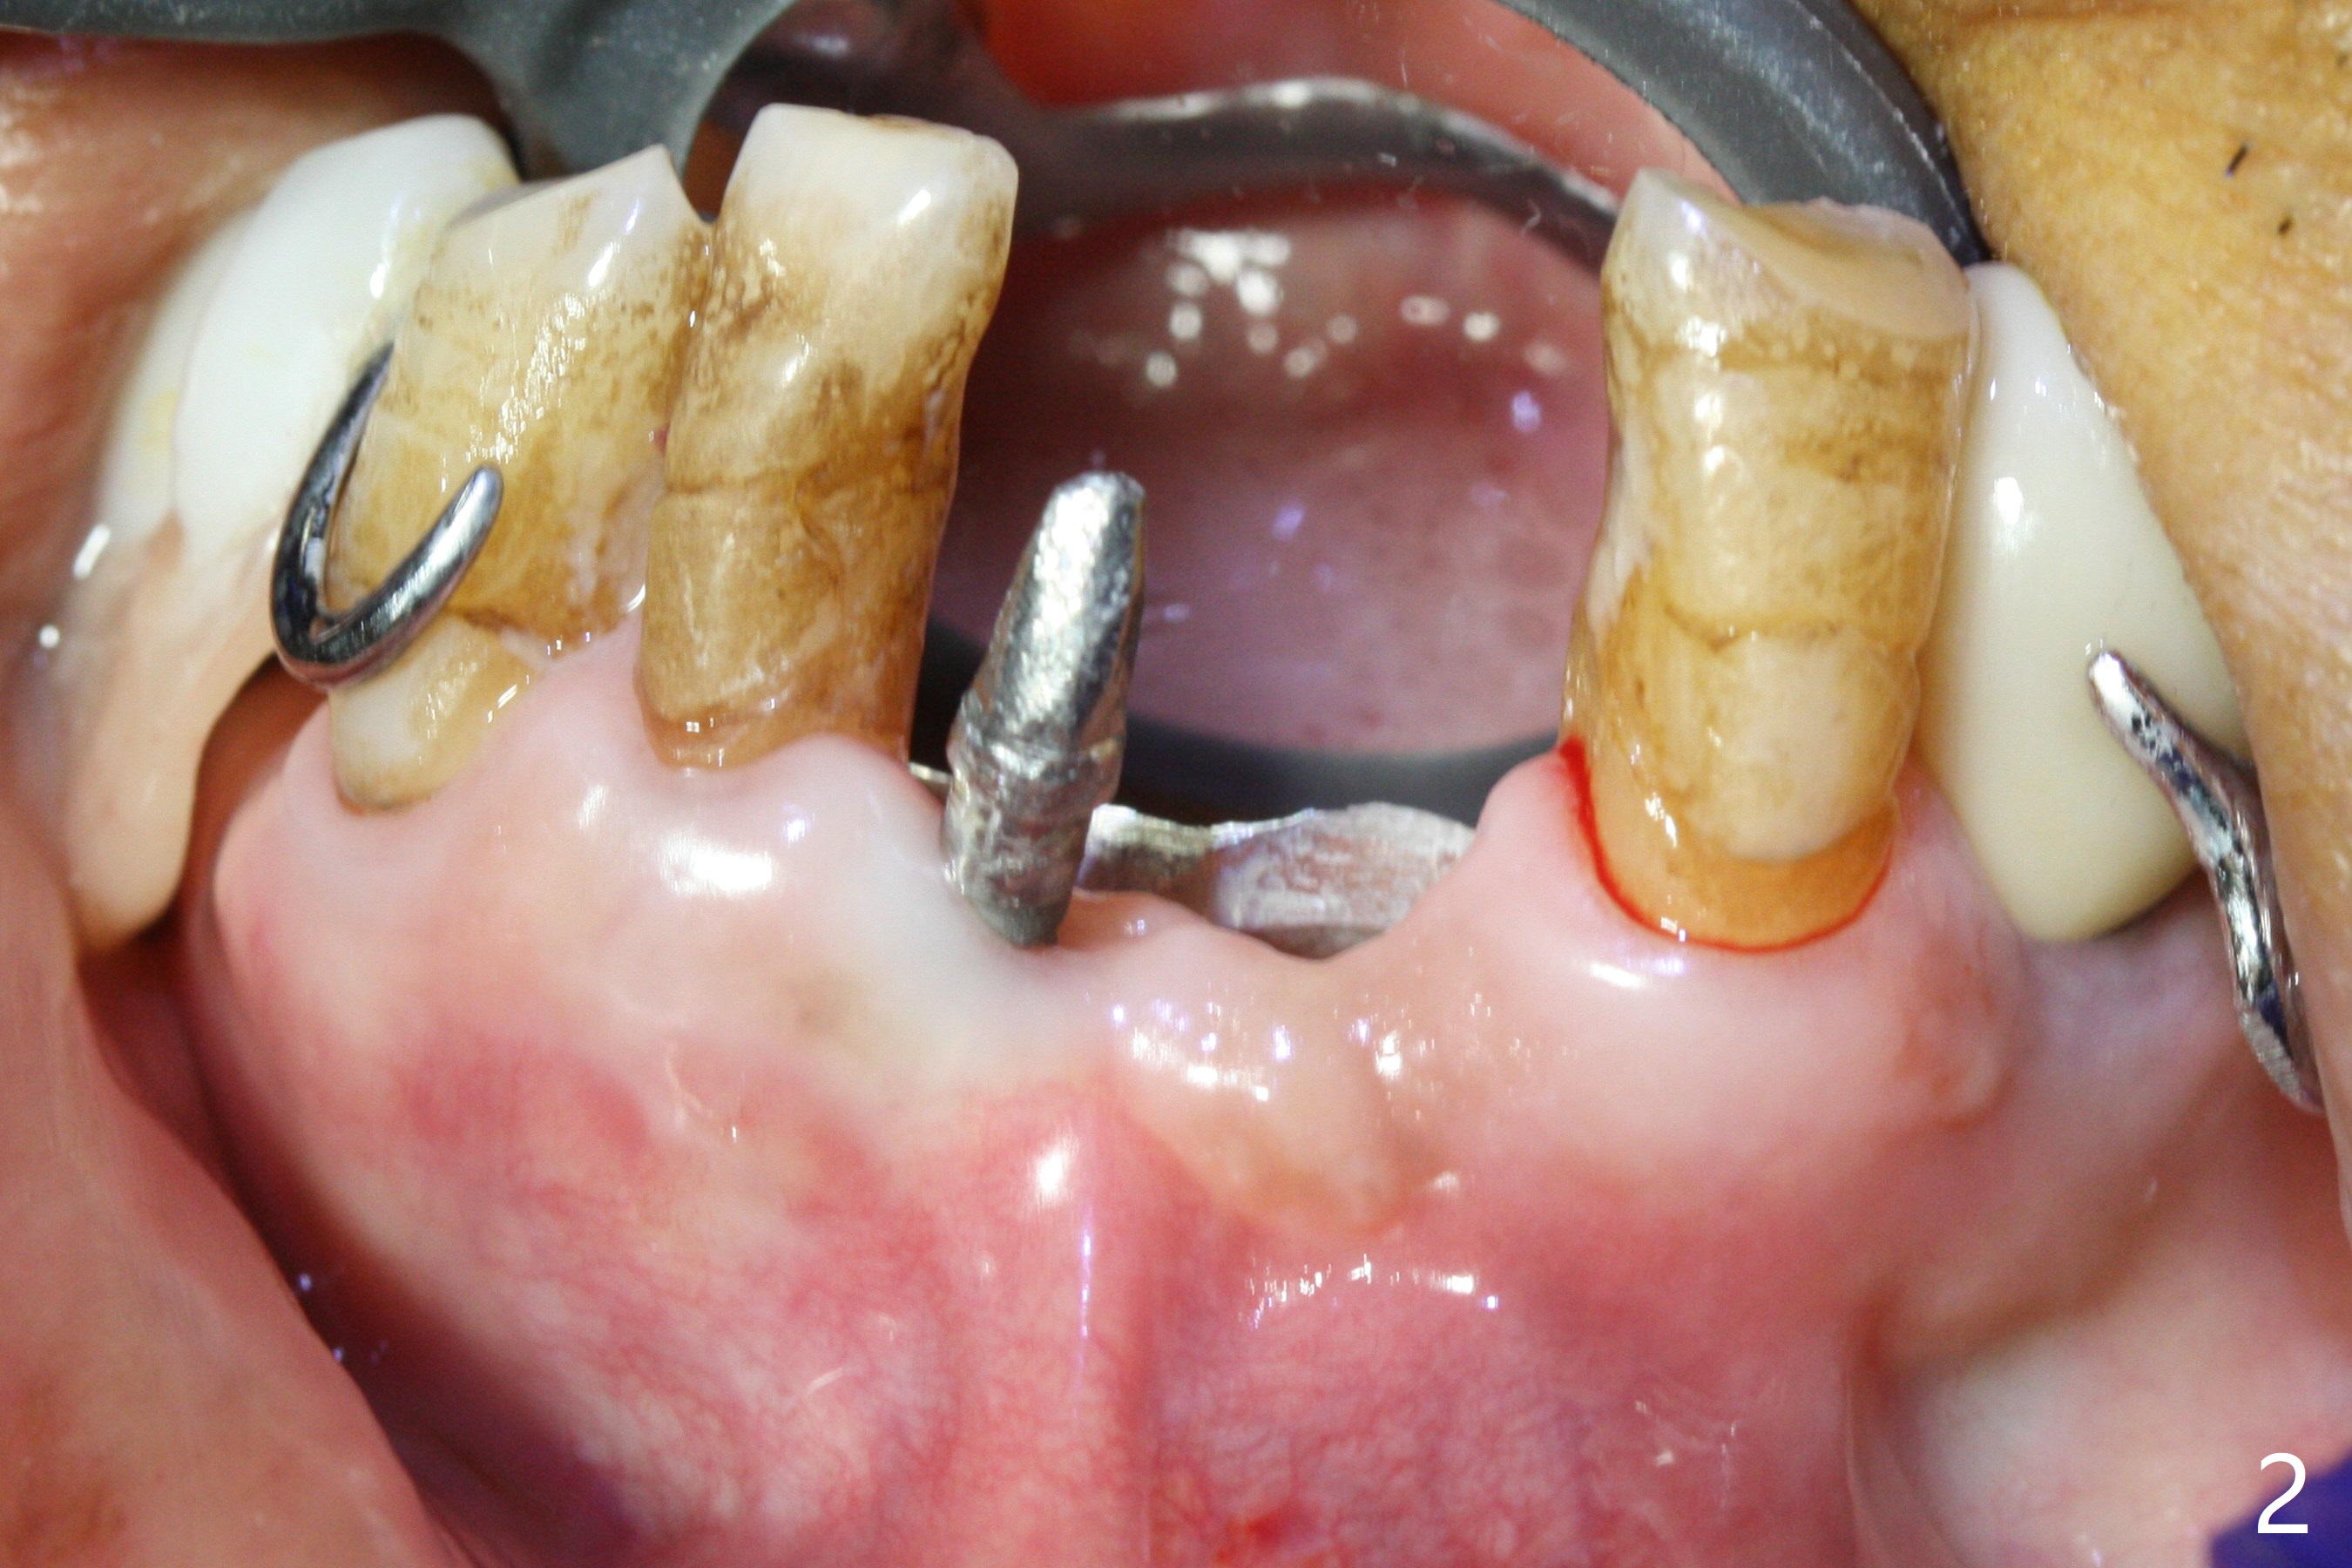

Two and a half months after loss of a 2 mm 1-piece approximately at #23 (Fig.1,2), it appears that the site of #24 (Fig.3 line) is more appropriate because the bone is higher. After removal of the pointed ridge top, osteotomy is initiated with 1.2 mm drill, followed by 1.5 mm one (Fig.4,5). When the 1.5 mm drill is removed, the new osteotomy (Fig.6 *) is mesial to the old one (^). Since the ridge is narrow (Fig.5,6), a 2x14(4) mm 1-piece implant is placed with GBR (Fig.7). Due to overprep, the torque is 20 Ncm. No immediate provisional is fabricated. Instead periodontal dressing is applied around these 2 implants. Two separate provisionals are fabricated when the wound heals. The one at #24 does not stay. The implant at #24 appears to osteointegrate 6.5 months postop (Fig.8). When the crowns are cemented, the margin is supragingival (Fig.9,10). Water Pik is recommended.